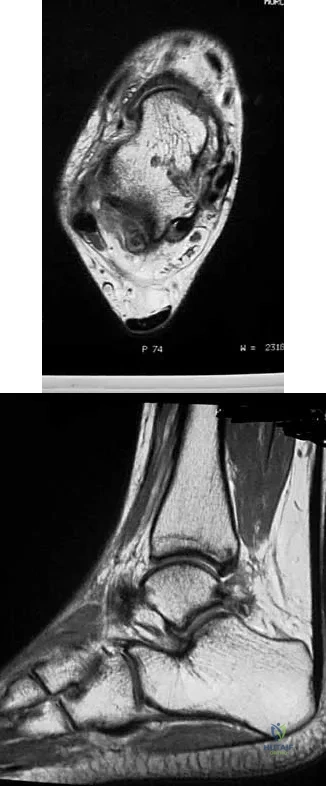

A 16-year-old female dancer has persistent posterior ankle pain, particularly after a vigorous dancing schedule. Examination reveals tenderness both posteromedially and posterolaterally. MRI scans are seen in Figures 44a and 44b. What is the most likely diagnosis?

Explanation